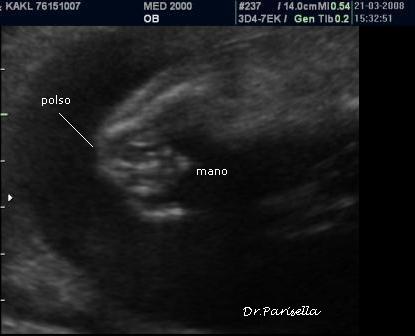

La diagnosi prenatale si basa su:

2) contratture articolari;